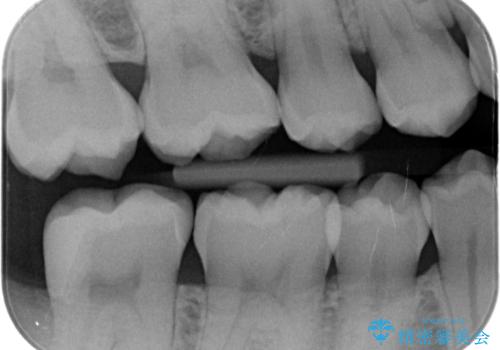

先に虫歯を徹底的に取り除き親知らずを抜歯してe-maxインレーで治療を行いました。

適合の良い詰め物が入りました。